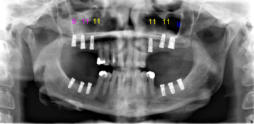

Beispiele für komplexe implantologische Versorgungen aus unserer Gemeinschaftspraxis

(Planung / Endversorgung -- als Röntgenaufnahmen)

C2